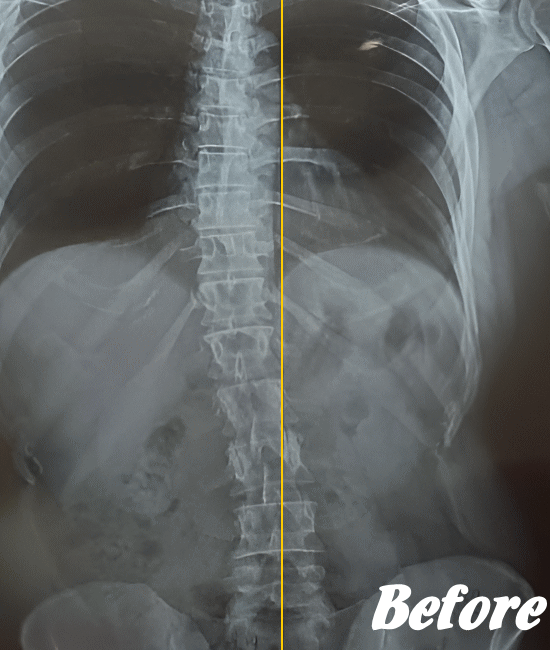

病院では、側弯の程度はレントゲンによる画像検査で弯曲の程度を調べます。

Cobb角(コブ角)とは、背骨の曲がり具合の角度を表す用語ですが、コブ角が10~25度程度なら経過観察。コブ角が25°~40°程度ならコルセットなどの装具を装着する療法、コブ角が40°~50°以上であれば手術…といった目安になります。

先天性や弯曲角度が大きい突発性側弯症は適応外になりますが、普段の姿勢の悪さに起因する機能性側弯症や初~中期の突発性側弯症であれば、施術対象になります。

ただし、弯曲が20°以上になると改善が難しくなってきます。また、脊柱(背骨)が側屈しているだけなら良いのですが、椎骨が回旋してしまっている場合の改善は、肋骨の変形もともなうため改善が難しくなります。